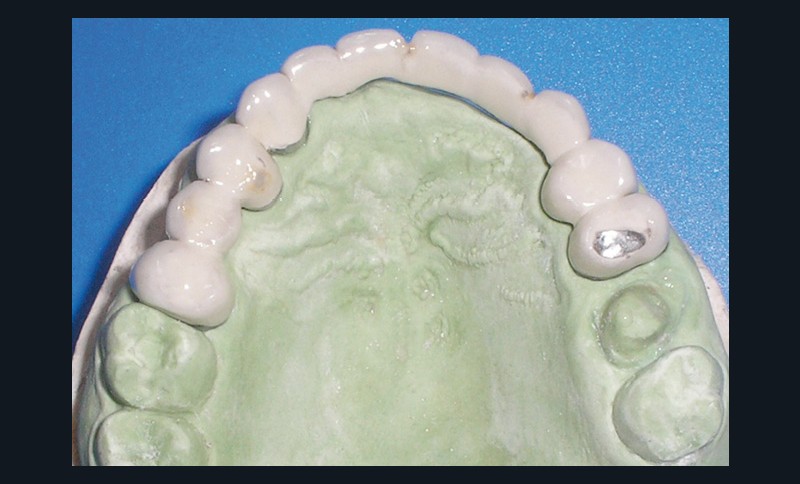

La patiente a été porteuse d’un bridge céramo-métallique de onze éléments au maxillaire pendant huit mois (fig. 1, 2), puis d’un bridge transitoire au maxillaire (fig. 3). Elle signale quelques rares épisodes de saignement probablement dus à l’irritation par la prothèse. Cette dernière se descelle couramment, créant ainsi un préjudice fonctionnel, esthétique et psychologique.